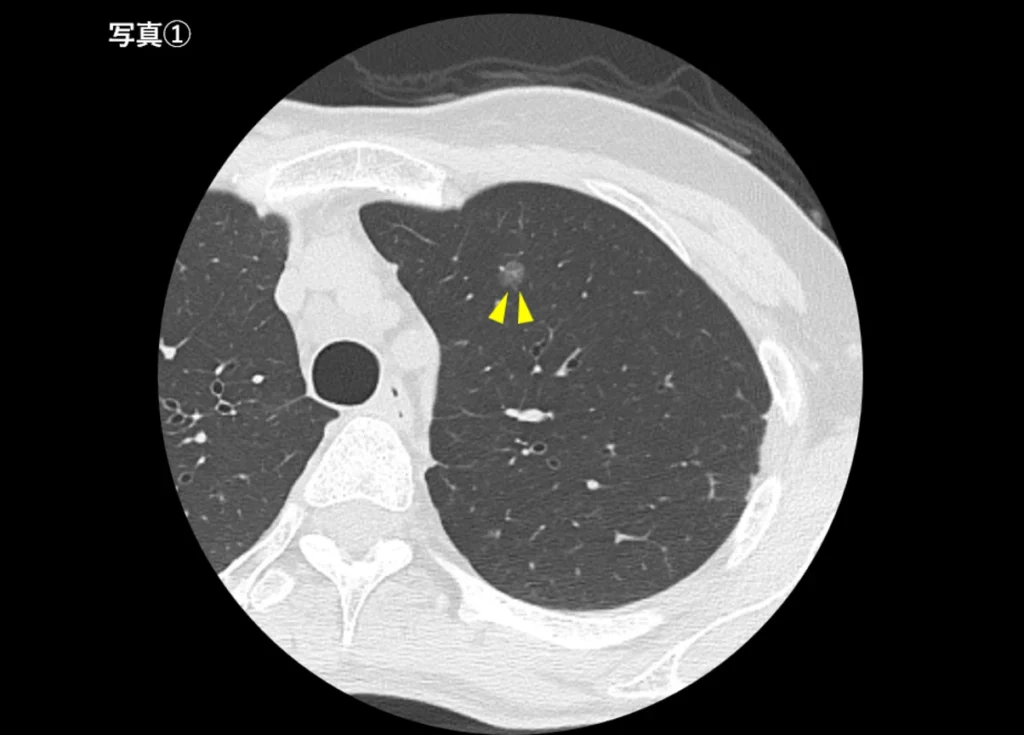

すりガラス影を伴う肺がん(写真①)

早期の肺がんでは、淡くぼんやりとした影として現れることがあります。このような病変はレントゲンでは見つけにくいことがあります。